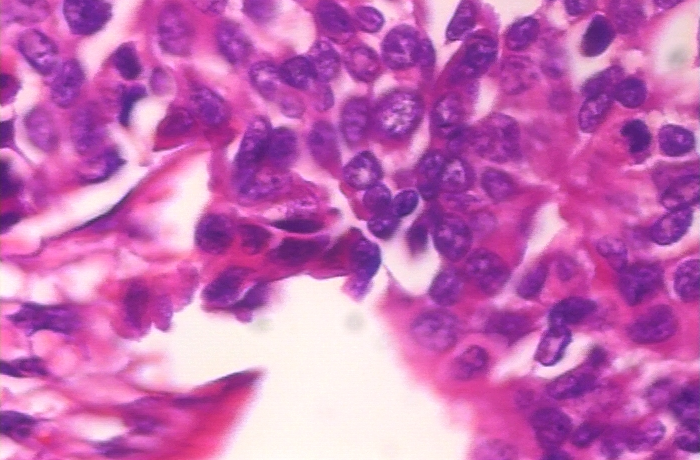

Refer to caption

(a) Malign image sample at 40x magnification.

(b) Malign image sample at 100x magnification.

(c) Malign image sample at 200x magnification.

(d) Malign image sample at 400x magnification.

Figure 2: Representative malign tissue image samples of the BreakHis dataset at different magnifications (40x, 100x, 200x, and 400x) for visual comparison.